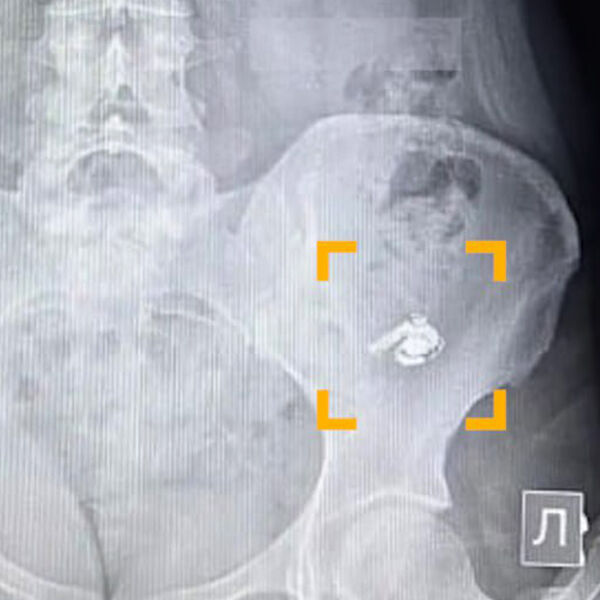

По словам уфимки по имени Мария, в момент глотания она почувствовала дискомфорт, но решила, что ей попалась крупная таблетка. Позже, обнаружив пропажу одного из наушников, девушка обратилась за медицинской помощью. В больнице ей сделали рентген, который подтвердил наличие инородного предмета в желудке.

Врачи решили не извлекать наушник, чтобы не спровоцировать осложнения, и рекомендовали дождаться его естественного выхода. Пациентку отпустили домой под наблюдение. Как рассказала Мария, устройство продолжало работать – при включении музыка воспроизводилась, однако услышать ее было невозможно.